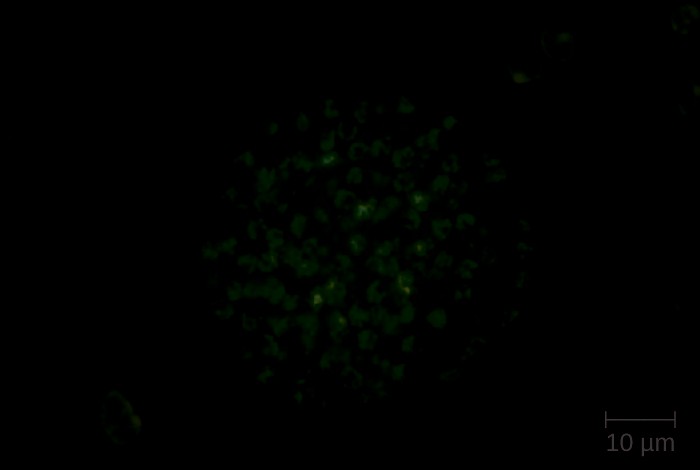

Figure 26.8 (a) Digitally colorized fluorescent antibody stained micrograph of Streptococcus pneumoniae in CSF. (b)

S. pneumoniae growing on blood agar. (credit a: modification of work by the Centers for Disease Control and Prevention; credit b: modification of work by Nathan Reading)